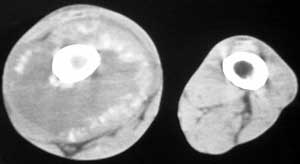

标题: CT4055:骨肉瘤?

男56涨疼5-6月

右股骨下端包绕股骨见巨大软组织肿块,密度部俊,周围见瘤骨,下端骨皮质侵蚀变薄,骨质周围无骨膜反应, 考虑右股骨软骨肉瘤。

右股骨下段周围软组织肿块伴钙化,相邻股骨骨皮质受累,考虑软组织来源恶性病变

右股骨下段骨肉瘤,软组织内瘤骨,软组织肿块。